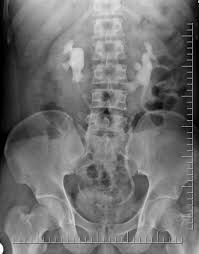

Kidney X Ray Images. The right kidney measures 10 7 cm and the left kidney measures 12 cm normal. This damage can be prevented by a feedback mechanism that determines the place of kidney stones depending on the images taken from eswl device.

Kidney x ray buy this stock illustration and explore similar illustrations at adobe stock. 0 public playlist includes this case. Until recently i ve only needed the nhs for short sharp interventions a tonsillectomy an appendectomy x rays and stitches. X rays are made by using external radiation to produce images of the body its organs and other internal structures for diagnostic purposes.